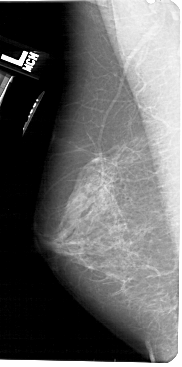

A_1520_1.RIGHT_MLO

RIGHT_MLO LINES 5491 PIXELS_PER_LINE 3001 BITS_PER_PIXEL 12 RESOLUTION 43.5 OVERLAY